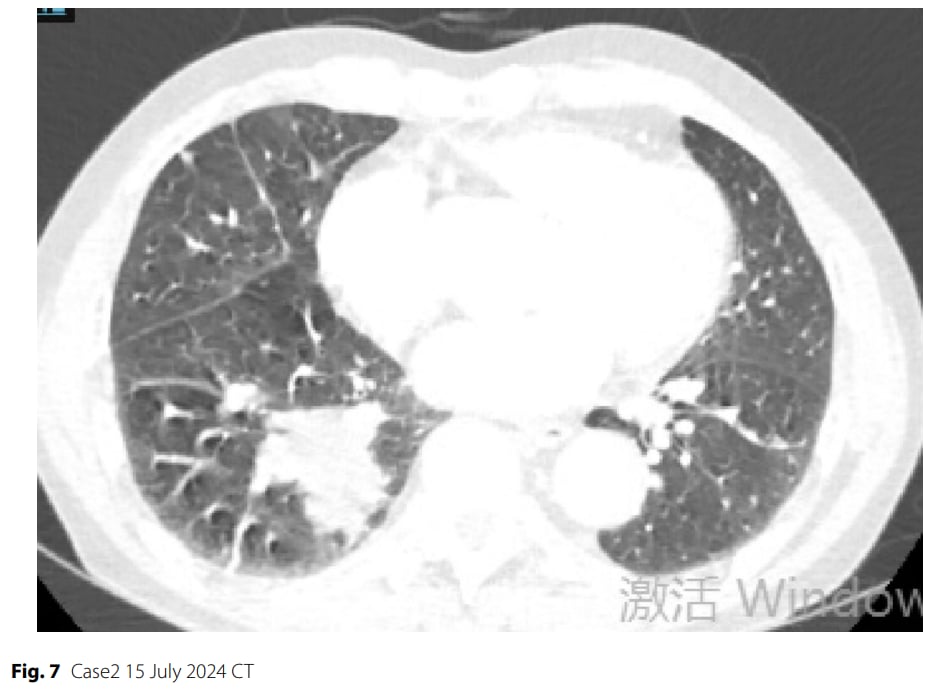

▲图7 病例2 2024年7月15日CT

治疗过程:患者接受了3个周期的“依托泊苷+卡铂+斯鲁利单抗”新辅助治疗。初期影像学显示肿瘤部分缓解(缩小68.3%),但第三个周期治疗后却出现反常进展(肿瘤增大)。影像学评估为疾病稳定(SD),具备手术切除条件。患者强烈要求手术,经多学科团队会诊,最终决定进行手术。随后患者接受了电视胸腔镜下肺叶切除术。